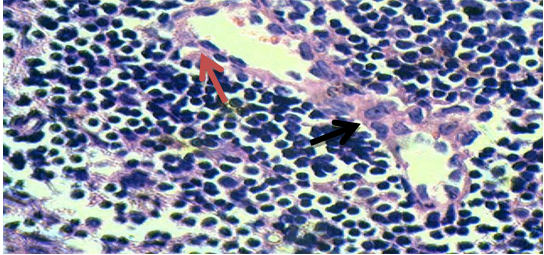

Fig. 2: Thymus section of group 2 (Extract control, 100 mg/kg), 40X

Few lymphocytes reveal destruction of structural integrity indicated by red arrow in fig. 2. Black arrow indicates normal lymphocytes in fig. 2.